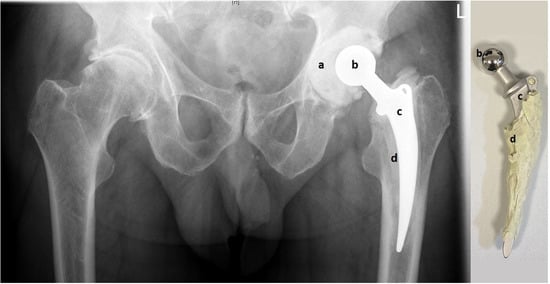

In all 23 cases, the metal-on-cement articulation was constructed using a 28 or 32 mm CoCr femoral head (S-2XL, DePuy Synthes, West Chester, PA, USA) with a corresponding femoral stem (Weber Stem CS/CM/SM, Zimmer, Warsaw, IN, USA) and a custom-made acetabular socket formed out of 40–80 g of antibiotic-loaded PMMA cement (Palacos cement, Heraeus, Hanau, Germany) with 3 g Vancomycin powder per 40 g of cement, as shown in Figure 1 (own unpublished data).

Figure 1.

Pelvic X-ray with articulating spacer in situ (left) and the same spacer after explantation (right). The custom-made acetabular socket (a) is made of antibiotic-loaded PMMA (polymethylmethacrylate) bone cement and creates the metal-on-cement articulation with the CoCr femoral head (b). PMMA bone cement (d) is also used to fix the femoral stem into the femur (c).